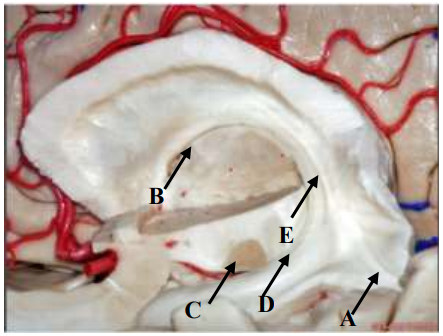

Qual seta aponta para o Nervo Facial?

Qual seta aponta para o Ponto Coroideo Inferior?